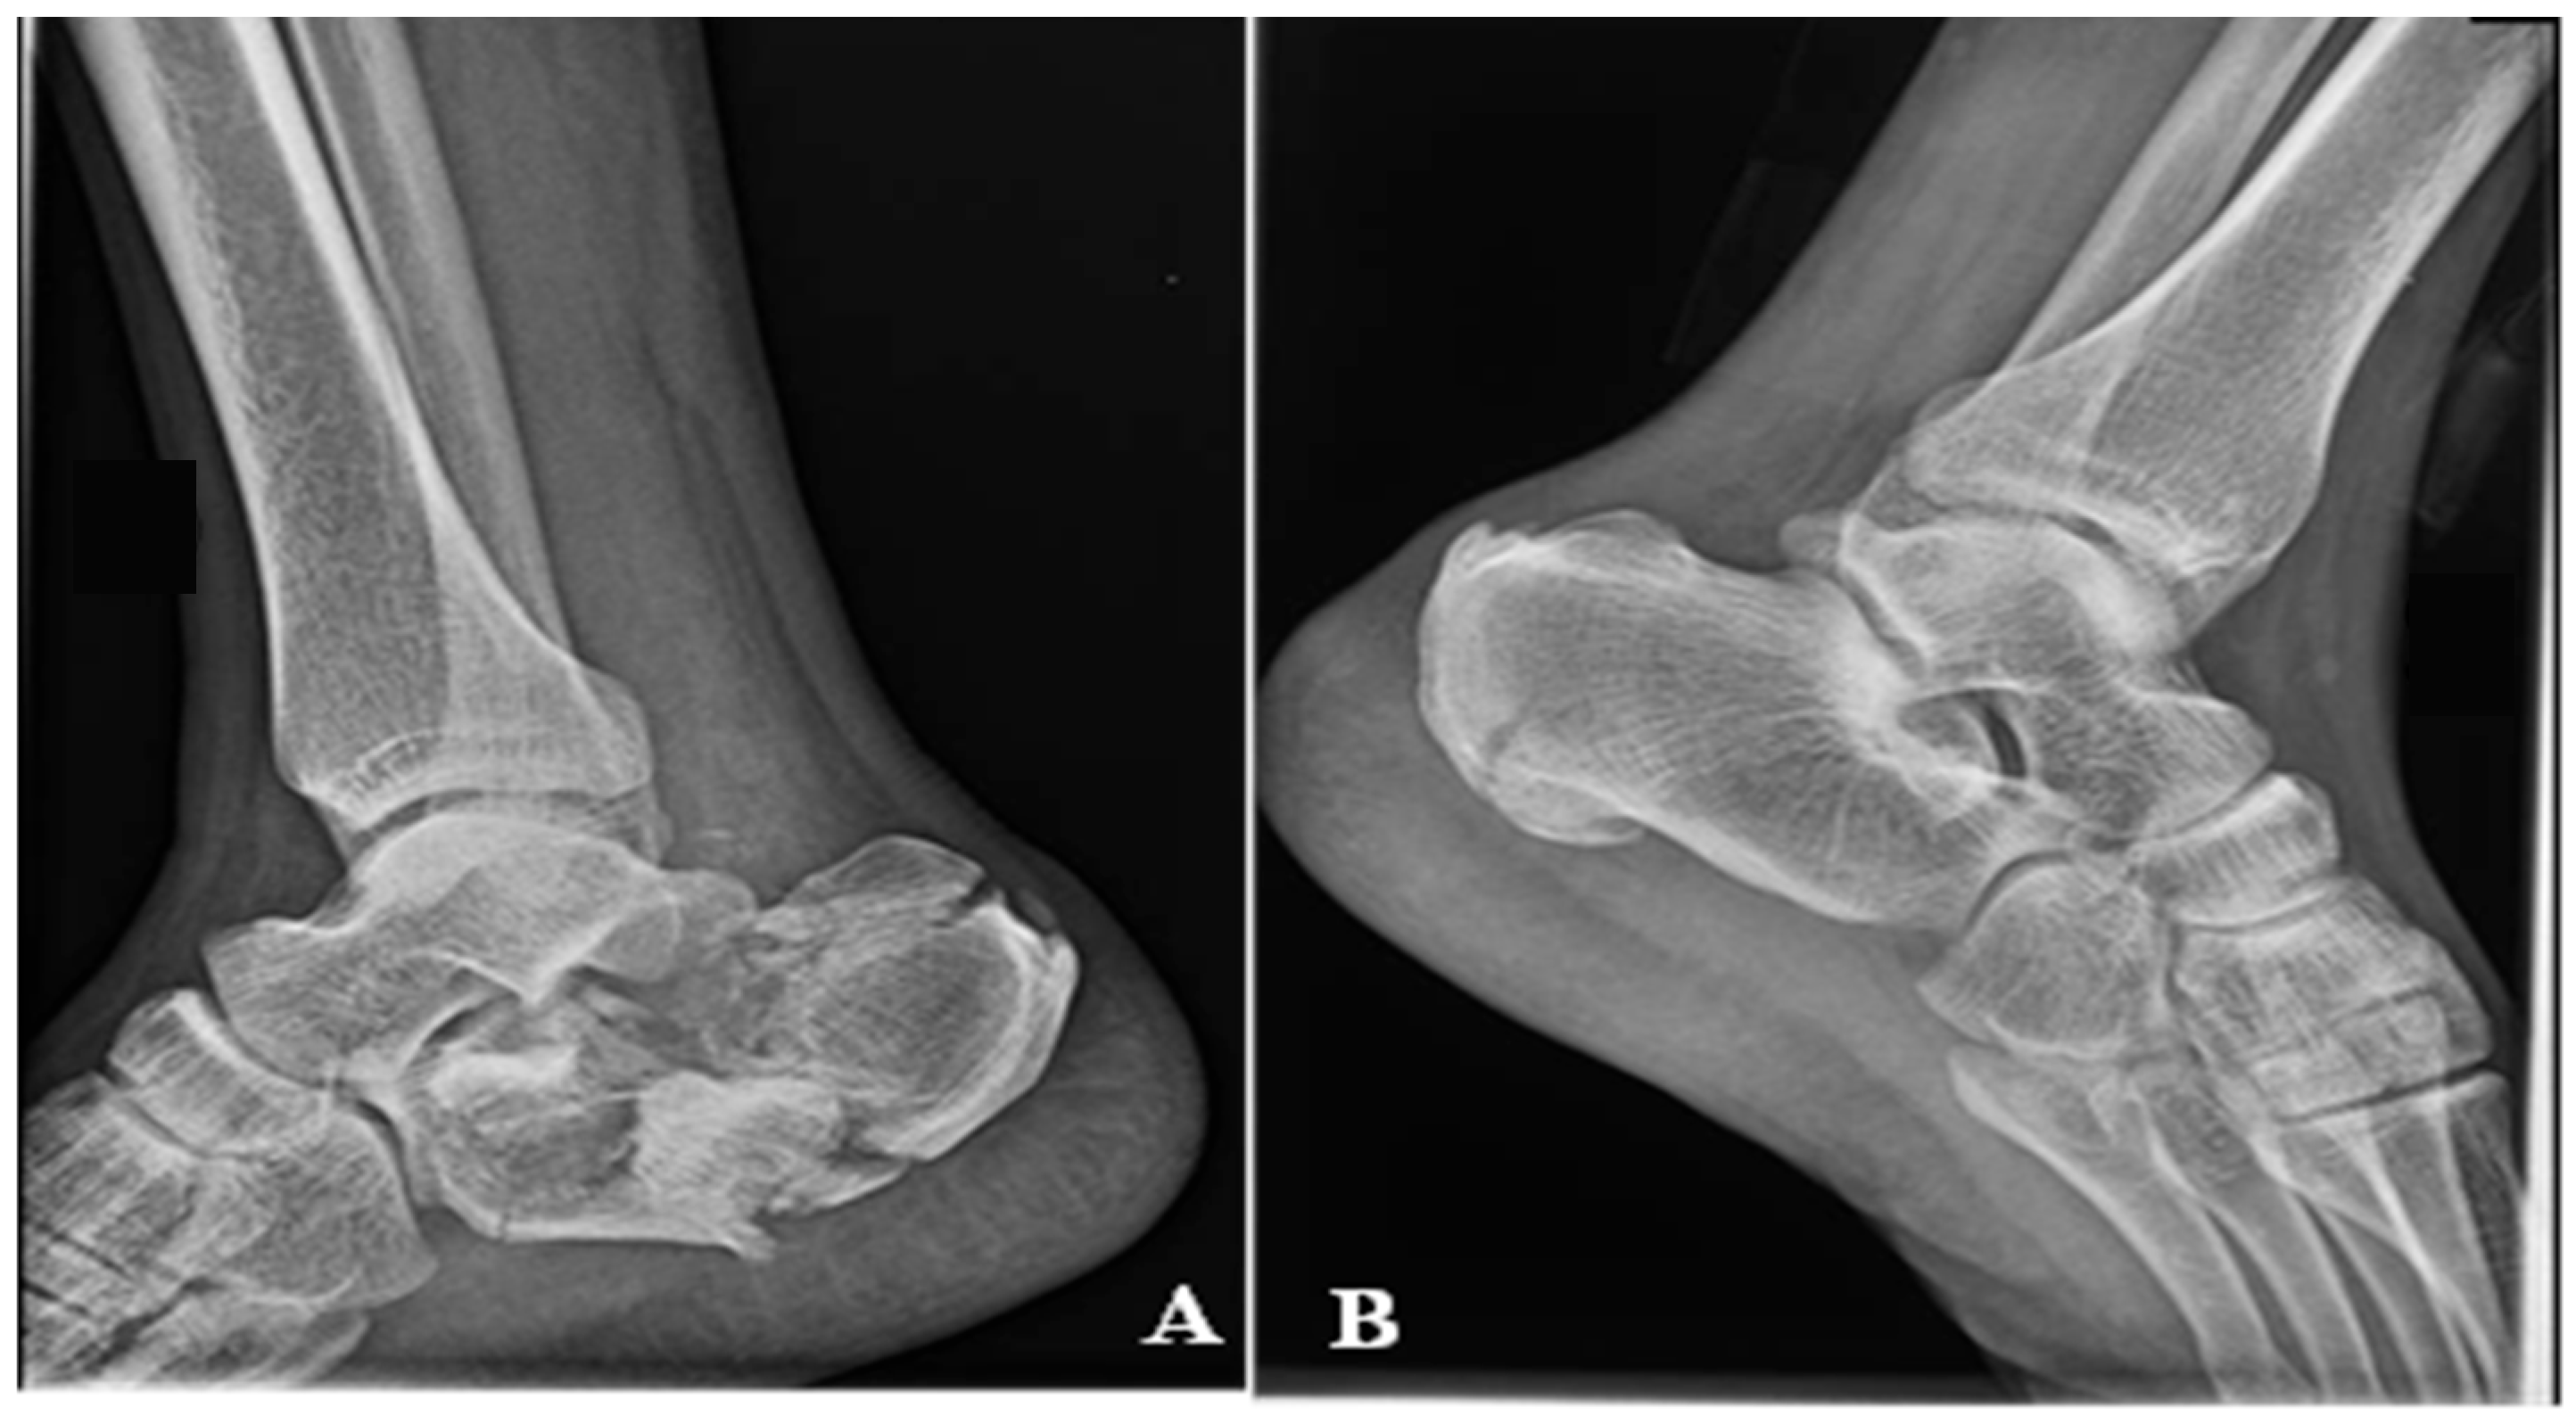

A 72-year-old male patient presents in the emergency room complaining of pain at the level of the right calcaneus, which started 3 weeks before when the patient sustained a fall from a ladder. The mechanism of the trauma was a combination of contusion at the level of the insertion of the Achilles Tendon and traction mixed with dorsiflexion of the foot. The pain was neglected, but at the level of the injury, the skin color started to change. The patient presented with an area of 5 cm × 5 cm of necrosis, acute pain in the dorsal aspect of the calcaneus, and the impossibility of full weight bearing and walking. The X-ray shows a calcaneal fracture (Müller/AO/OTA classification: 82-A1). Figure 8. The soft tissue area covering the calcaneal tuberosity presented this alteration of vascularization because of the fracture fragment attached to the Achilles tendon, which was pulled backwards and upward, generating pressure on the soft tissue from the inside.

Figure 8. (A) Necrosis of the soft tissue covering the fracture site, 3 weeks after fracture. (B) X-ray of the ankle.